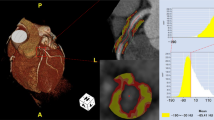

Perivascular fat analysis

PCAT was extracted automatically by using the Skviewer software FAI intelligent analysis system (Skviewer FAI; Shukun Technology, Beijing, China) [12]. The volume and FAI of PCAT were measured using the method described by Oikonomou et al. [7]; the threshold value of PCAT ranged from − 190 to − 30 HU, the measured length was 40 mm, and the extracted radial distance was the average diameter of the target vessel. The segment analyzed was the proximal 40 mm of the left anterior descending (LAD) and left circumflex (LCX) arteries and the proximal 10–50 mm of the right coronary artery (RCA). The software could extract PACT volume and FAI automatically, and when the automatic extraction was inaccurate, we adjusted the extraction range manually. Subsequently, the PCAT volume and FAI were calculated by the software automatically (Fig. 2). The above measurement results were completed by an experienced radiologist independently. In order to test the consistency of the measurement results, 20% (32) of patients were randomly selected 1 month later, and a second measurement session was carried out by 2 radiologists. An intraobserver consistency test was carried out on the results measured by the same doctor, and an interobserver consistency test was carried out on the results measured by 2 doctors (Additional file 1).